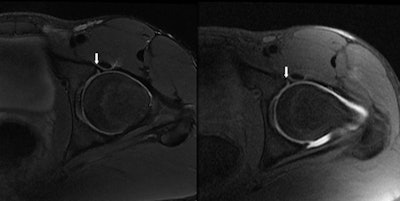

| Image shows an acetabular labral tear (arrows) via an MR image (left) and MR arthrogram (right). No additional information was needed. All images courtesy of Dr. Thomas Magee. |

The analysis showed that MR arthrography detected acetabular labral tears in 72 of the 100 patients, while MRI discovered acetabular labral tears in 71 patients.

Thirty-eight of the 100 patients were sent for arthroscopy, where their labral tears were confirmed. Conventional 3-tesla MRI found 37 of the acetabular labral tears on those 38 patients, while all 38 MR arthrograms diagnosed the acetabular labral tears in the same patient group.